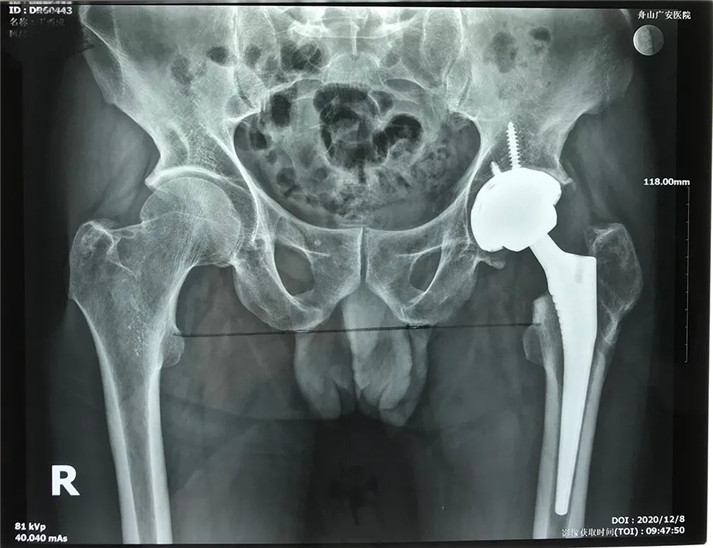

考慮到患者的年齡、骨折類(lèi)型等情況,以及患者的種種擔(dān)憂(yōu),為精準(zhǔn)治療、加快愈合、避免關(guān)節(jié)脫位及肢體長(zhǎng)短不等,羅軍主任團(tuán)隊(duì)采用了近期引進(jìn)的AI HIP置換術(shù)前規(guī)劃系統(tǒng)為患者行術(shù)前規(guī)劃。他們將丁先生的術(shù)前CT數(shù)據(jù)導(dǎo)入到系統(tǒng)中,通過(guò)自動(dòng)識(shí)別骨盆和股骨建立了計(jì)算機(jī)數(shù)字三維模型。AI HIP顯示患者適合使用合適的髖臼杯、股骨柄、標(biāo)準(zhǔn)陶瓷球頭、陶瓷內(nèi)襯,并精準(zhǔn)定位了截骨線(xiàn),可以有效幫助醫(yī)生在手術(shù)中做到精確截骨。

經(jīng)過(guò)周密的術(shù)前準(zhǔn)備,在身體符合手術(shù)指征后,丁大哥接受了全髖關(guān)節(jié)置換術(shù)。術(shù)中發(fā)現(xiàn)術(shù)前規(guī)劃產(chǎn)生的假體大小、位置、角度均非常理想,大大縮短了手術(shù)時(shí)間,全程十分順利。術(shù)后,丁先生恢復(fù)良好,次日即可下床活動(dòng)。目前術(shù)后一個(gè)月,可以干活了。對(duì)于此次手術(shù),丁大哥及其家屬表示非常滿(mǎn)意。

術(shù)后

傳統(tǒng)的髖關(guān)節(jié)置換存在手術(shù)精準(zhǔn)度低、手術(shù)風(fēng)險(xiǎn)大、并發(fā)癥多、成本高、效率低等問(wèn)題,同時(shí),髖關(guān)節(jié)置換中需要考慮五大變量,目前的術(shù)前規(guī)劃低效、誤差大,而人工智能術(shù)前規(guī)劃則可以解決這些問(wèn)題。人工智能術(shù)前規(guī)劃分為三維重建、人工智能識(shí)別與分割、人工智能矯正與測(cè)量、假體預(yù)放置4個(gè)步驟。人工智能術(shù)前規(guī)劃精度高、位置好、三維成像、操作方便等優(yōu)勢(shì),是目前的前沿技術(shù)。

“精確的術(shù)前規(guī)劃是術(shù)后良好效果的一大保證,而AI HIP 人工智能輔助關(guān)節(jié)置換術(shù)前規(guī)劃系統(tǒng)可在術(shù)前規(guī)劃出最適合患者的假體材料、假體型號(hào)以及假體安放位置,測(cè)量誤差僅在1mm以?xún)?nèi),真正實(shí)現(xiàn)精準(zhǔn)定制化的術(shù)前規(guī)劃,具有提升術(shù)前規(guī)劃精準(zhǔn)性、縮短手術(shù)時(shí)間、降低手術(shù)風(fēng)險(xiǎn)及并發(fā)癥等優(yōu)勢(shì),可以說(shuō)是廣大髖關(guān)節(jié)疾患患者的福音。”羅軍主任表示。